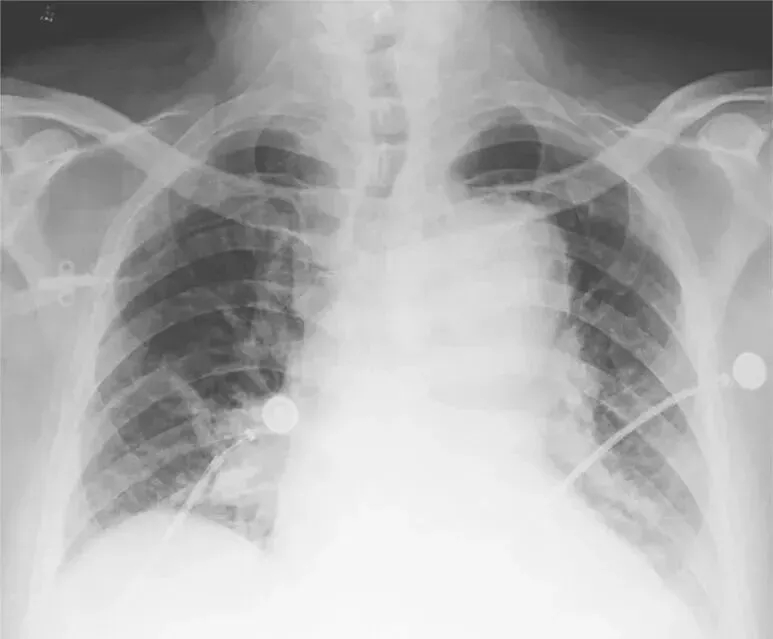

随着64层螺旋CT出现后,使冠状动脉、肺动脉及主动脉血管同时成像成为可能,即一站式多层螺旋CT检查。多排螺旋CT具有无创、快速等优势,并且具有丰富的图像后处理软件,是急性胸痛三联征的病因筛查及确诊的有效手段,具有卓越的临床应用价值。该检查技术就是扩大胸部扫描范围,调整扫描参数和对比剂注射量及注射速度,同时得到主动脉、冠状动脉及肺动脉影像信息,影像医师应用工作站进行图像后处理,可以运用曲面重建(curved planar reconstruction,CPR)、最大密度投影(maximum intensity projection,MIP)、多平面重建(multi-planar reconstruction,MPR)、容积再现(volume rendering,VR)等对冠状动脉、肺动脉、主动脉及肺部进行观察。胸痛三联征一站式扫描技术的重点就是为急诊医师提供短时、高效、可靠的诊断信息,对降低患者并发症、病死率十分关键。《中国胸痛中心认证标准》(第5版)规定:胸痛中心应具备多排螺旋CT增强扫描的条件,并能开展急诊主动脉、肺动脉CTA检查,从启动CT室到接受患者进行检查的时间在30分钟以内。恰当运用多层螺旋CT检测不仅可以明确危及生命的胸部动脉疾病原因,指导治疗,还可以实现非常高的潜在的成本效益。主动脉夹层在影像学上典型的表现如图4。

如果在某一层面看到管腔中的低密度线影不连续,或是对比剂将两个管腔沟通,就可以判定夹层破口的位置(图5)。

图4 主动脉夹层导致纵隔影增宽

图5 主动脉夹层破口位置